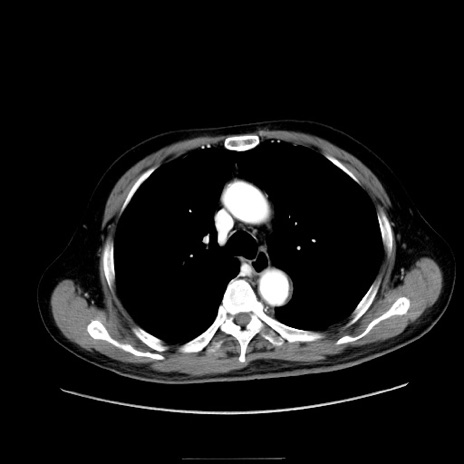

冠状断像